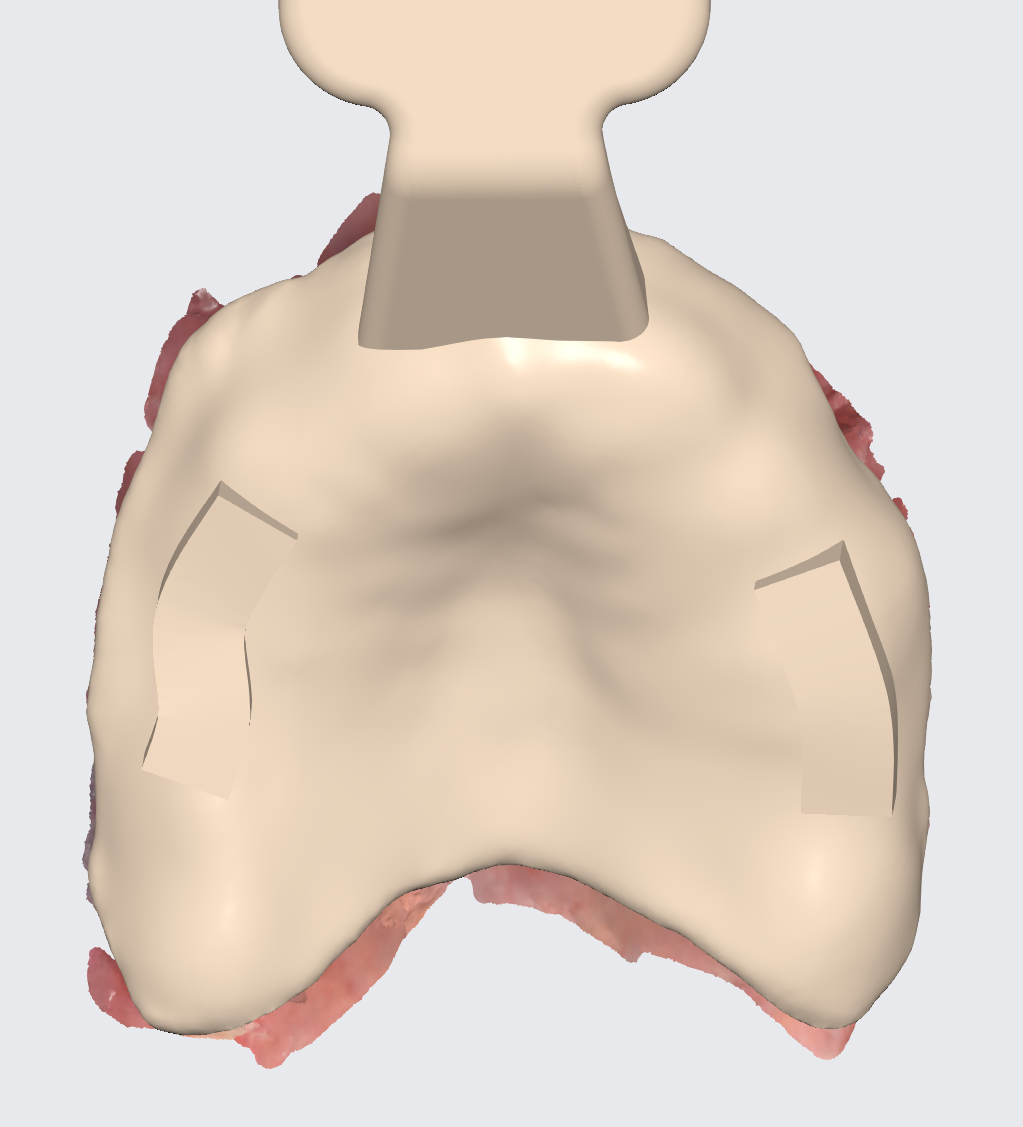

A modified full arch guide was produced that allowed for implant placement with a flapped approach and no tissue punching for preservation of fixed soft tissue and visual verification of maxillary bone.

Guides produced in Exoplan . Irrigation is easily achievable and soft tissue can be repositioned to not get harmed by the burr .